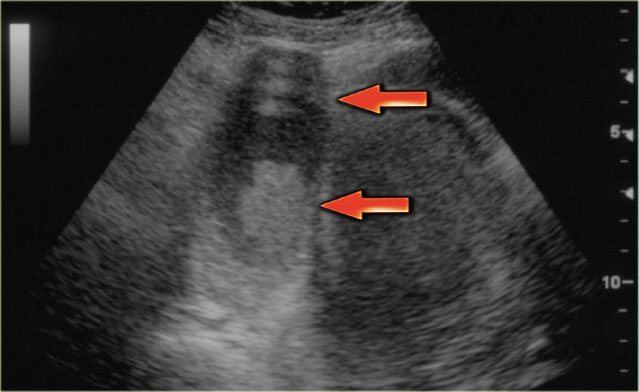

Hemorrhagic ovarian cyst in both right and left ovary Hemorrhagic ovarian cyst in both right and left ovary

The ultrasound images show the right and left ovary: on both sides there is what appears to be a solid lesion.

There is however good through transmission, which indicates that we are probably dealing with hemorrhagic cysts.

On Doppler US (not shown) there was no vascularity.

Continue with the MR examination.

Hemorrhagic ovarian cyst Hemorrhagic ovarian cyst

On an axial T1-weighted image both lesions are bright indicating fat, blood or high protein fluid.

Fat saturation does not suppress the signal in these lesions.

In an image with overall reasonably good fat suppression this rules out a fat-containing teratoma and confirms the suggestion of hemorrhagic fluid.

On the axial T2-weighted image both lesions show typical 'shading'.

The gradual drop in T2 is thought to be caused by a combination of increasing viscosity and increasing concentration of protein and iron towards the dependent portion of the lesion.

There is no enhancement on the subtraction image (Post-Gd minus Pre-Gd).

Again, subtraction is useful in cases like this: Gd-induced signal increase over the already very bright pre-contrast image would be very hard to appreciate otherwise.